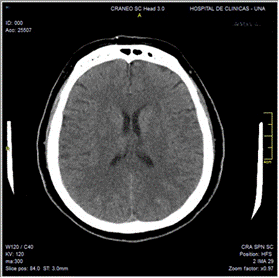

Se solicita analítica laboratorial con el retorno de los siguientes valores: Hb 11.8 g/dL, Hto 33,1 %, GB 10 280/mm3, N 70 %, Plaquetas 352 000/µL, Urea 42 mg/dL, Creatinina 0,13 mg/dL, Na 142 mEq/L, K 3,4 mEq/L, Cl 108 mEq/L, Ca 9,5 mg/dL, P 5,8 mg/dL, Mg 2 mg/dL, BT 0.32 mg/dL, BD 0,11 mg/dL, GOT 21 UI/L, GPT 30 UI/L, TP 99,8 %. Se realiza TAC de cráneo y cuello simples más RMN con contraste de encéfalo y angiorresonancia de encéfalo, sin constatarse particularidades. Además, se realiza nasofibrobroncoscopía, describiéndose hallazgos dentro de la normalidad (Figura 2a, b).